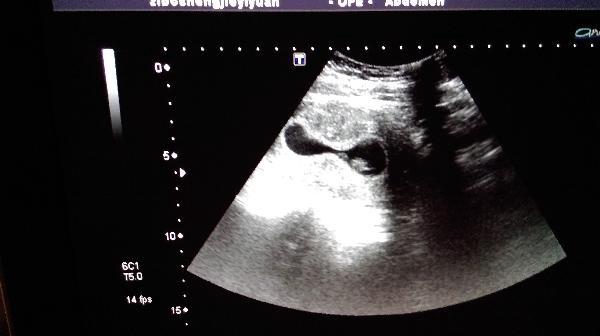

早孕9周妊娠囊这个形态怎么报?

妊娠囊近似葫芦状,胎芽、胎心、卵黄囊正常。孕妇原有子宫腺肌症,有痛经病史。

只要胎心正常,见卵黄囊,我们也认为是正常,妊娠囊的形态和膀胱充盈程度也有关系